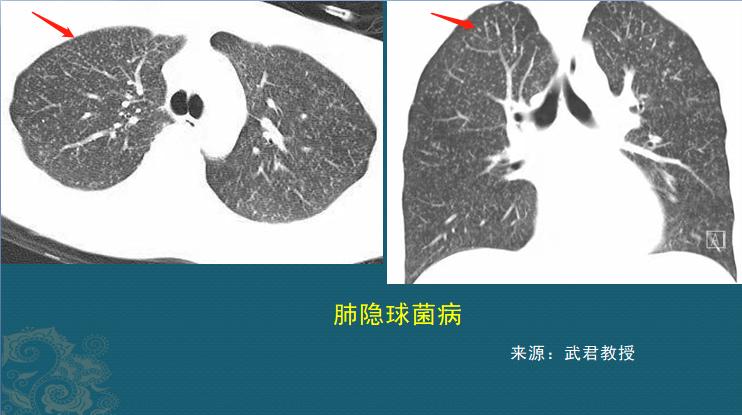

实际上,肺隐球菌病除了上面这种肺结节型的表现之外,在CT片上还有两种常见的表现:肺炎型和粟粒性肉芽肿型。

1.结节肿块型,表现为单发或多发的结节或肿块(肉芽肿性炎),边界清晰或者伴有晕征,当伴有晕征时提示意义较大。需要留意:这种类型常常被误诊为肺癌或者肺结核,因为它也常出现毛刺、空洞、支气管截断征等等,我们后面会讲鉴别诊断。